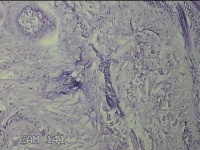

后颈部皮肤结节

性别

男

年龄

45岁

临床诊断

皮肤结节病

一般病史

发现后颈部皮肤结节半年余。

标本名称

大体所见

灰白粉红色组织1.7x0.9x0.3cm一块,表面带梭形皮肤1.7x0.9cm,皮下见结节1.5x1.1cm一个,切开结节呈实性,切面灰白粉红色,质软。

图4